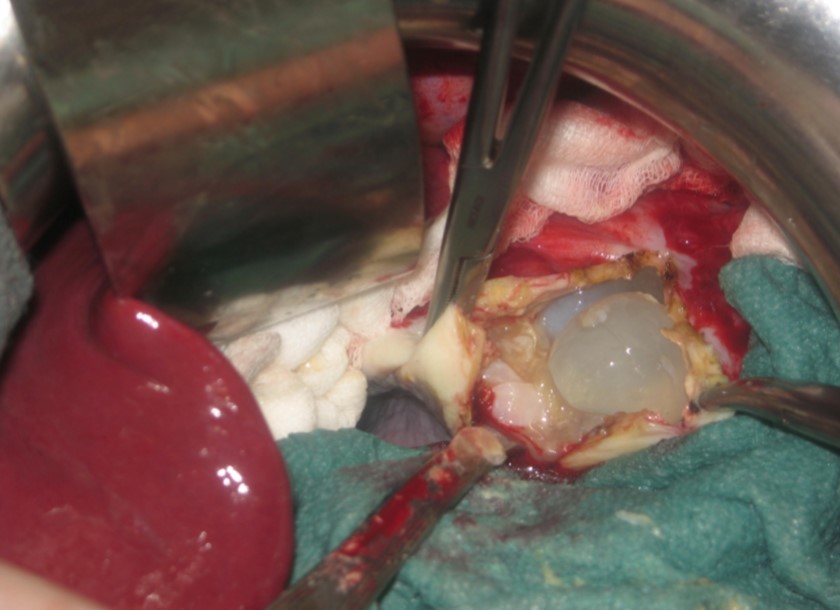

A 17-year-old young man admitted to our department with the complaint of abdominal pain localized in the left upper quadrant for the last 3 months. His physical examination revealed a splenomegaly. Immunoblot assay for Echinococcus was positive. His laboratory tests showed normal results of the serum and urine examinations, No eosinophilia was found. Chest X-ray revealed no pathological signs. An abdominal ultrasonography showed a 20 cm multivesicular cystic mass of spleen (figure 1). Contrast enhanced CT scans detected a huge single 20×16×18cm cystic mass located in the spleen. It had well-defined borders and contained multiple, round, daughter cysts in the periphery of the lesion with calcification (Figure 2, Figure 3, Figure 4). The patient underwent a laparotomy. A large splenic cystic mass was identified, attached to diaphragm, and tail of the pancreas (figure 5). The abdomen was packed with 10% hypertonic saline soaked pads in order to protect peritoneal soilage. A partial cystectomy without splenectomy was performed. Histologic examination of the specimen resection showed an echinococcal organism residing within the hydatid cyst . The patient was discharged after 4 postoperative days. 600 mg per a day of Albendazole therapy was instaured postoperatively and continued for 6 months. Two years after surgery the patient is well with disease free.

Figure 5.Intraoperative view showing multivesicular spleen hydatid cyst.

Intraoperative view showing multivesicular spleen hydatid cyst.